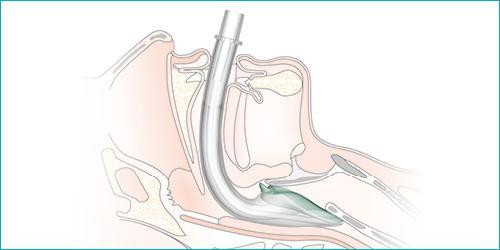

Nasopharyngeal Airway (NPA)

• The nasopharyngeal airway is a soft flexible tube designed to open a channel between the nostril and the nasopharynx.

Nasopharyngeal airways

Nasopharyngeal airway in situ

• They are bevelled at the insertion end and flanged at the outer end. If the outer flange is shallow, a safety pin can be fastened at the end of the tube to prevent them passing completely into the nose.

• NPA tubes are usually better tolerated by conscious or semi-conscious children. They are available in a number of sizes but generally do not cater for smaller paediatric patients. In which case a shortened endotracheal tube (ETT) can be used.

• The correct sized tube is estimated by measuring from the nostril to the tragus of the ear. The appropriate diameter can be estimated by measuring against the size of the nostril. The NPA should fit snuggly but not cause blanching of the nostril.

• To insert, the NPA should be lubricated, then inserted into the nostril in the direction that it will lie. With a gentle rotation motion the NPA should be passed directly backwards and posteriorly to sit in the nasopharyngeal space.

• Contraindications to using an NPA are facial trauma, basal skull fracture, coagulopathy and nasal obstruction.